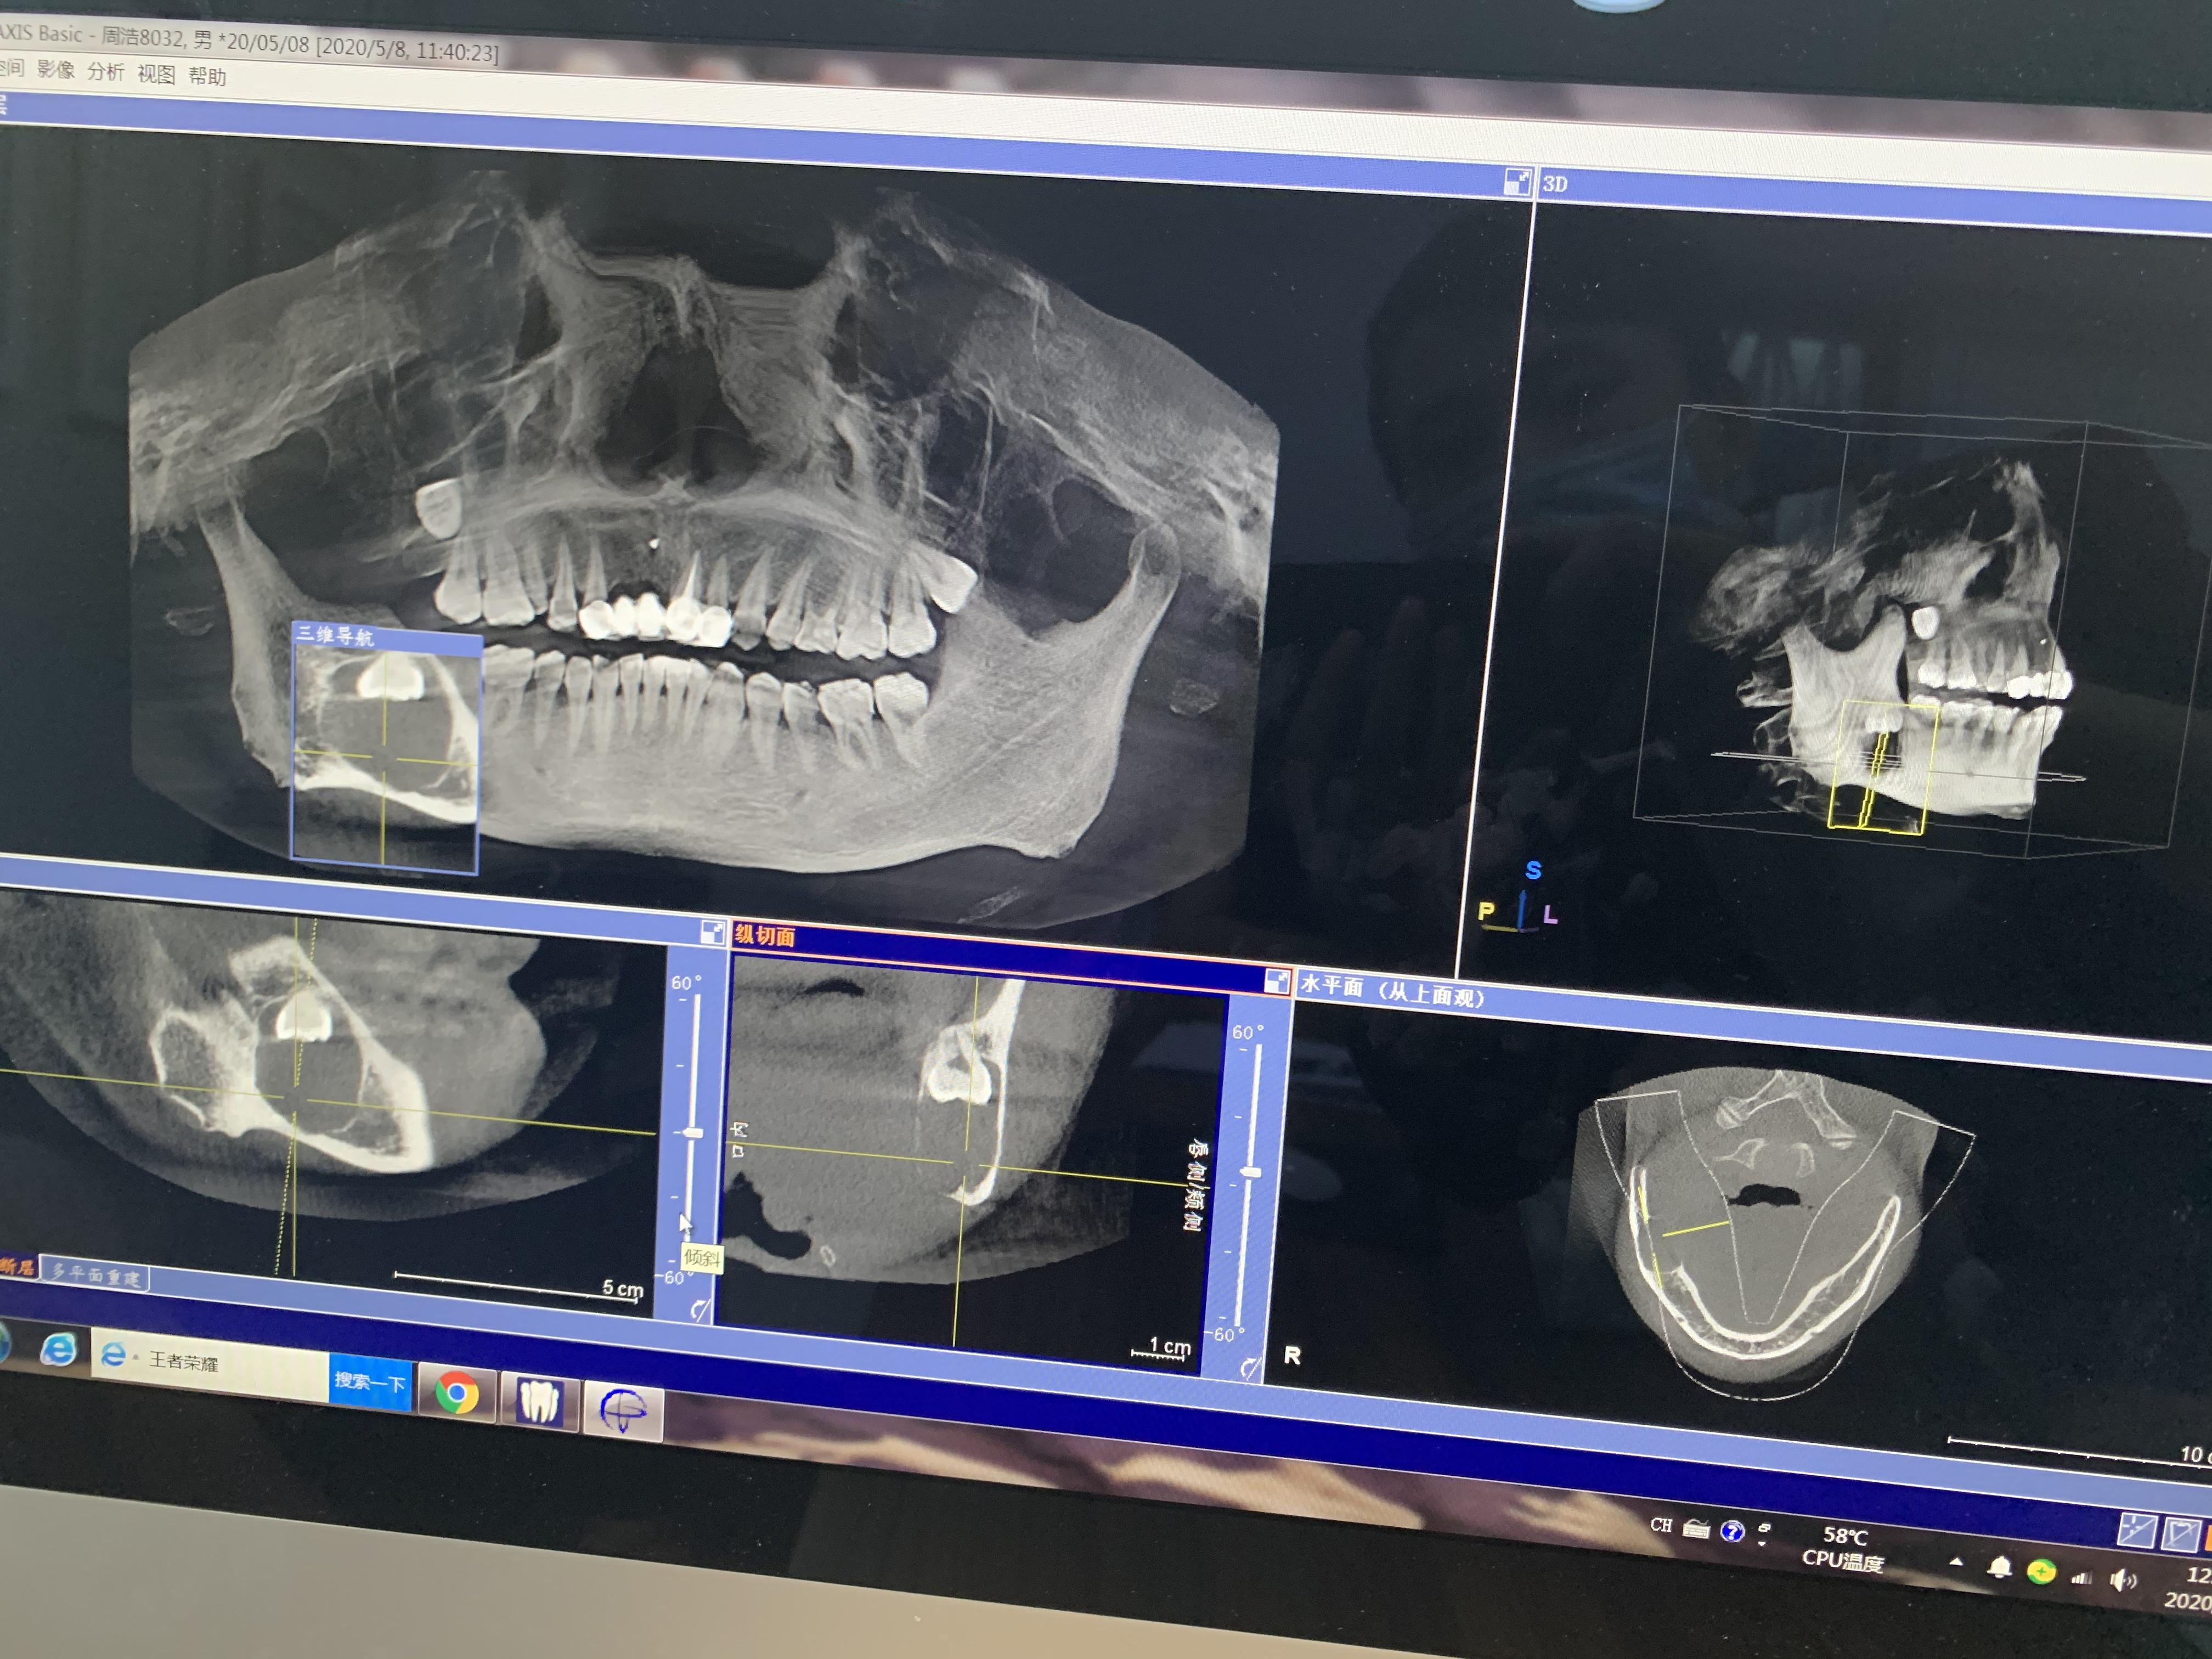

方框內(nèi)圓形的就是囊腫,從邊緣看,骨頭已經(jīng)很薄了

右下頜囊腫,倒阻生牙